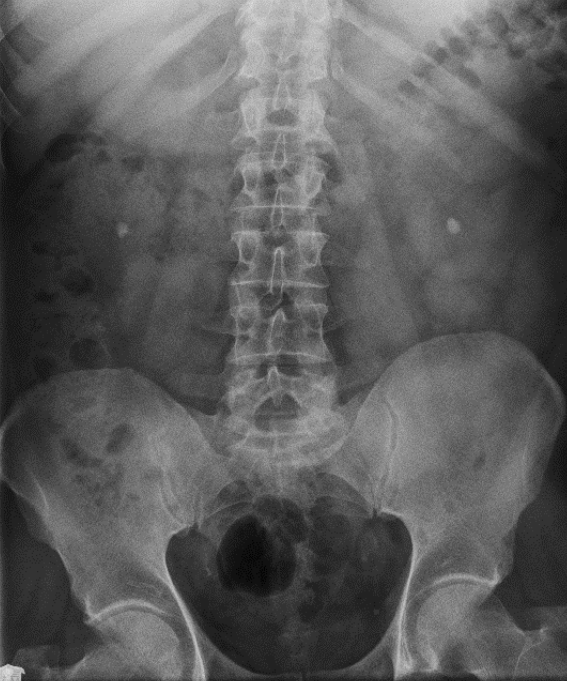

Które badanie zostało zarejestrowane na przedstawionym radiogramie?

Ilustracja do pytania 21

A. Jamy brzusznej wykonane poziomą wiązką promieniowania.

B. Płuc wykonane metodą Przybylskiego.

C. Układu moczowego z użyciem środka kontrastującego.

D. Dróg żółciowych metodą cholangiografii śródoperacyjnej.